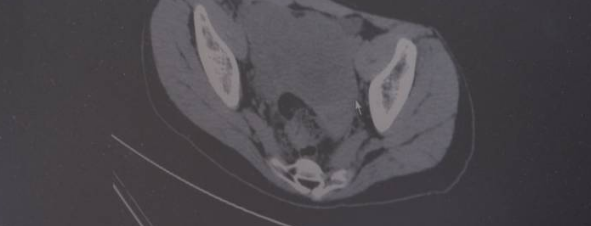

CT画面显示,盆腔里有一个大的实性的肿瘤,占据整个盆腔的二分之一以上,最大的直径将近20厘米。正常的卵巢都已经看不到了,被肿块全部占据了。

晴晴属于卵巢癌四期,也就是晚期,好在癌细胞没有转移到其他重要器官。医生立刻对晴晴进行了手术。目前晴晴术后情况良好,后续将会接受化疗。